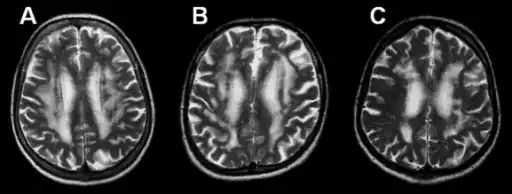

MRI-a-c)Three brains with the pure pathology of Binswanger's disease

Leukoaraiosis refers to the imaging finding of white matter changes that are common in Binswanger disease. However, leukoaraiosis can be found in many different diseases and even in normal patients, especially in people older than 65 years of age.[6]

There is controversy whether leukoaraiosis and mental deterioration actually have a cause and effect relationship. Recent research is showing that different types of leukoaraiosis can affect the brain differently, and that proton magnetic resonance spectroscopy would be able to distinguish the different types more effectively and better diagnosis and treat the issue.[10] Because of this information, white matter changes indicated by magnetic resonance imaging or computerized tomography cannot alone diagnose Binswanger disease, but can aid to a bigger picture in the diagnosis process. There are many diseases similar to Binswanger's disease including CADASIL syndrome and Alzheimer's disease, which makes this specific type of white matter damage hard to diagnose.[6] Binswanger disease is best when diagnosed of a team by experts including a neurologist and psychiatrist to rule out other psychological or neurological problems.[4] Because doctors must successfully detect enough white matter alterations to accompany dementia as well as an appropriate level of dementia, two separate technological systems are needed in the diagnosing process.

Much of the major research today is done on finding better and more efficient ways to diagnose this disease. Many researchers have divided the magnetic resonance imaging of the brain into different sections or quadrants. A score is given to each section depending on how severe the white matter atrophy or leukoaraiosis is. Research has shown that the higher these scores, the more of a decrease in processing speed, executive functions, and motor learning tasks.[15][16] Other researchers have begun using computers to calculate the percentage of white matter atrophy by counting the hyper-intense pixels of the magnetic resonance images. These and similar reports show a correlation between the amount of white matter alterations and the decline of psychomotor functions, reduced performance on attention and executive control.[17][18] One recent type of technology is called susceptibility weighted imaging (SWI) which is a magnetic resonance technique which has an unusually high degree of sensitivity and can better detect white matter alterations.[19]